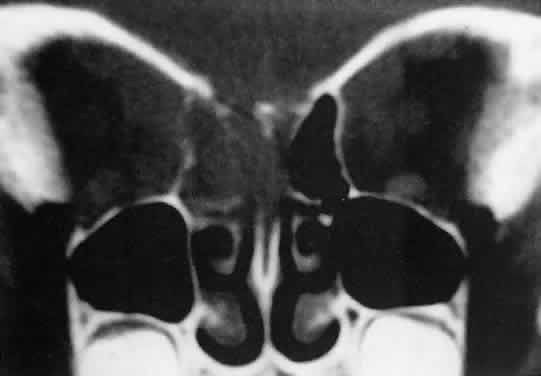

The intimate association of orbital lymphangiomas with structures critical to normal vision makes their complete excision almost impossible without incurring vision loss. Because their vascular components do not actively proliferate, the response to radiation therapy is limited and probably is proportionate to whatever lymphoid tissue is present. The presence of a blood cyst is not in itself an indication for treatment if vision is not impaired. In many cases, the blood resorbs during several weeks without residual problems. Frequently, however, vision is compromised by the sudden expansion of multilobulated cysts that surround the optic nerve, and simple observation may result in permanent deficits. Treatment requires evacuation of the offending cysts in a conservative manner consistent with preservation of vision.84 Because the channels of a lymphangioma are hemodynamically isolated from the systemic circulation (“no flow anomalies”),63 their surgical decompression does not produce brisk new bleeding from within them. Rather, the hemorrhagic risk of surgery involves intraoperative and, more often, postoperative, intrinsic bleeding, creating new blood-filled macrocysts.62 Conservative surgery restricts intraorbital manipulation, involves evacuation of offending blood cysts, and avoids disturbance of nonexpanded portions of the lymphangioma. Extensive dissection for cosmetic purposes should be undertaken with the same respect for the fragility of nonexpanded channels. TRAUMATIC ORBITAL HEMATOMA Although the diagnosis of a traumatic orbital hematoma would seem obvious on the basis of history alone, some element of trauma within a few days of the onset of proptosis is such a common historical finding among small children that it may have little differential value. Conversely, a history of culpable trauma may not always be forthcoming, as in cases of child abuse. In penetrating orbital injuries, the entry wounds suggest the diagnosis. Retained foreign bodies should be ruled out. In blunt injuries, other diagnostic clues are helpful. Ecchymosis may be present but also may be a feature of granulocytic sarcoma, neuroblastoma, or lymphangioma with recent bleeding. CT may show an associated fracture. Most orbital hematomas that result from blunt injury occur in the potential subperiosteal space (Fig. 18). The lack of adjacent sinus opacification and the absence of systemic toxicity differentiate this entity from a subperiosteal abscess, which can have a similar appearance.59 Echography shows the low acoustic reflectivity characteristic of fluid-filled spaces. If a traumatic orbital hematoma has compromised vision by acutely elevating orbital pressure, the pressure should be reduced promptly with a lateral canthotomy and cantholysis. If, conversely, vision is compromised because of extreme globe displacement and optic nerve attenuation, the hematoma should be evacuated.87 This is a relatively simple procedure if the blood is compartmentalized in the subperiosteal space. We favor a lid crease incision, with dissection between orbicularis muscle and orbital septum to the orbital rim. The subperiosteal space is then entered, and the hematoma is evacuated. If vision is not compromised, patients can be treated conservatively. Spontaneous absorption generally follows, but hematomas occasionally enlarge with osmotic imbibition. DERMOID CYST Dermoid and epidermoid cysts often occur in the orbit and paraorbital region. Epidermoid cysts are lined by stratified squamous epithelium and are filled with desquamated keratin. The walls of dermoid cysts include dermal appendages that contribute sebum, sweat, and hair shafts to the cyst contents. Both forms probably result from abnormal invagination of surface ectoderm during fetal development. Differences may relate to the depth of tissue that has been sequestered or to the degree of ectodermal differentiation at the time of inclusion.88 Most dermoid cysts are closely related to bone suture lines, suggesting that the surface ectoderm has been trapped between fusing mesodermal processes. Dermoid cysts are most often encountered at the frontozygomatic articulation but can occur at other suture lines, including those deep in the orbit. Most lesions are anterior and paraorbital (Fig. 19), located between the orbicularis muscle and the periosteum overlying the orbital rim, and have a fibrous stalk to the suture line. Anterior cysts produce minimal bone change. Other lesions may be entirely intraorbital, causing proptosis and globe displacement. Their expansion produces an overall increase in orbital volume as well as local bone changes (Fig. 20). Dermoid and epidermoid cysts also may be largely intradiploic, with expansion into the anterior cranial fossa, the temporal fossa, or the orbit. Dumbbell lesions may be present with narrow intraosseous components. Anterior, paraorbital dermoid cysts usually are evident soon after birth. Deeper lesions may not declare themselves until mid- or late childhood, or even the adult years. Expansion of the cysts generally is slow and linear, reflecting continuous desquamation of keratinizing epithelium. There may be a point at which the pressure within the cyst inhibits further proliferation and sloughing of epithelial cells, accounting for the clinically observed stability of many lesions. Sporadic enlargement may be caused by hormonally influenced sebaceous gland secretion or by rupture of the cyst wall with a granulomatous inflammatory response to the cyst contents (see Figs. 19B-D). Such episodic change in an otherwise gradual growth pattern places intraorbital dermoid cysts into the current differential diagnosis. Anterior lesions generally are diagnosed and removed without difficulty, although their occasional occurrence near the lacrimal excretory system can complicate treatment.89 Surgeons should strive for excision of an intact cyst, because residual epithelial elements can lead to recurrence. CT examination of deeper lesions discloses a cystic mass with some internal heterogeneity caused by the different radiodensities of keratin clumps and oily secretions (see Fig. 20B). Bone changes, from shallow fossas to spherical defects, are smooth, with a sclerotic margin and a punched-out appearance. Based on the CT findings, the differential diagnosis includes cholesterol granuloma and unifocal eosinophilic granuloma. Superomedial orbital dermoid cysts must be distinguished from meningoencephaloceles before surgical intervention. Most intraorbital cysts can be removed through a lateral or anterior orbitotomy. The walls of deep lesions may be intimately attached to adjacent bone and may not peel off intact. Gentle use of a high-speed steel burr can facilitate complete removal of the cyst lining. ANEURYSMAL BONE CYST Aneurysmal bone cyst is an uncommon, benign tumor-like lesion of unknown origin.90 Most lesions present in the second decade with pain and swelling. Any bone may be involved, but the long bones and vertebrae are most often affected. Aneurysmal bone cyst of the orbital roof is an unusual cause of rapidly progressive proptosis.91 In one case, a 16-month-old boy was affected.92 The lesions both erode and expand cancellous and cortical bone.90 They are surrounded by a shell of periosteal new bone that prevents their extension into soft tissue. MRI may show fluid-fluid levels indicative of hemorrhage.92 In some cases, aneurysmal bone cyst appears to be a pathophysiologic change superimposed on a pre-existing lesion, such as a giant-cell tumor.90 In most cases, however, the bone cyst is considered a distinct pathologic and radiologic entity. Treatment of facial lesions with intralesional resection or curettage has a substantial rate of recurrence. Recurrence can be reduced with marginal resection or cryotherapy. INFLAMMATORY PSEUDOTUMOR Idiopathic inflammatory pseudotumor (IIPT) is a general term applied to those orbital inflammations without an identified inciting agent and with a sparsely cellular, mixed inflammatory infiltrate that does not suggest a systemic disease. Despite efforts to replace the pseudotumor designation, the term remains entrenched in the literature.93 However, the spectrum of clinical and pathologic conditions included under the rubric has been narrowed and refined since the term was first applied a century ago. IIPT can occur in the first 2 decades of life as well as in adulthood, and it may affect children as young as 3 years of age.94 There appears to be no sex predilection. The condition can be subdivided topographically into myositis, dacryoadenitis, episcleritis/tenonitis/perineuritis, and a localized mass. However, combined forms are common, and even when the process is centered in one structure, inflammatory changes appear microscopically and in imaging studies to spill into adjacent tissues. Among these variants, orbital myositis and dacryoadenitis are the most common forms of IIPT encountered in children. Local tumefactions may occur anywhere in the orbit. When they involve the crowded orbital apex or superior orbital fissure, they can produce the Tolosa-Hunt syndrome of painful ophthalmoplegia. The typical patient with IIPT has an abrupt onset of pain, proptosis, eyelid edema, chemosis, and conjunctival vascular engorgement.94 The left orbit is affected twice as often as the right, but bilateral orbital involvement, either simultaneous or separated by variable intervals, occurs in almost half of the pediatric cases. Among children with IIPT, there is a higher incidence of iritis than among adults with this disorder. Optic nerve head edema is noted in one-third of cases. Systemic complaints are variable but may include fever, malaise, anorexia, and nausea. Orbital symptoms may follow an upper respiratory tract infection. In pediatric cases, laboratory abnormalities may include peripheral blood eosinophilia and elevations of the erythrocyte sedimentation rate, complement level, and antinuclear antibody titer.95 The absence of a marked leukocytosis with a left shift should help differentiate this condition from bacterial orbital cellulitis. Orbital myositis may represent a greater proportion of cases of IIPT in childhood than in adulthood, and involvement of multiple extraocular muscles may occur more frequently in children than inadults. In orbital myositis, early diplopia and increased discomfort with attempted eye movement are typical symptoms. CT may show enlargement of one or more extraocular muscles in one or both orbits (Figs. 21 and 22). When a single muscle is involved, the specter of a primary or metastatic neoplasm within the muscle may be raised. However, external inflammatory signs, considerable pain and limited motility, and an explosive onset of symptoms within 24 hours all suggest orbital myositis. The uniform enlargement of the muscle, including its tendinous insertion (see Fig. 22), also helps distinguish the process from a neoplasm, which might be expected to produce a more focal, globular expansion. Echography may support the diagnosis of inflammation by showing edema in the episcleral space as a relative sonolucency between the scleral and orbital fat echoes (Fig. 23). Its CT counterpart is an increase in the radiodensity and thickness of the ocular tunica.

In dacryoadenitis, external inflammatory signs are localized to the superotemporal quadrant, and CT shows enlargement of the lacrimal gland (Fig. 24). Lacrimal gland inflammation may be bacterial, viral, or a variant of IIPT. It is possible, however, that many cases of “idiopathic” dacryoadenitis represent unidentified viral infections. In bacterial dacryoadenitis, a leukocytosis with a left shift may be present.96 In questionable cases, a 1-week course of oral antibiotics can be administered to these patients. Among children, the probability that an enlarged lacrimal gland represents neoplasia rather than inflammation is lower than among adults, although epithelial lacrimal gland tumors occasionally may occur in the pediatric population and can produce external inflammatory signs. If the general signs and symptoms of IIPT are lacking, a biopsy should be performed. Histopathologically, IIPT is characterized by a sparse, mixed inflammatory cell infiltration of the tissues primarily involved (i.e., extraocular muscle, lacrimal gland, Tenon's fascia). The predominant cell is a mature lymphocyte, but there are significant numbers of polymorphonuclear neutrophils, plasma cells, and eosinophils.95 As the inflammatory process evolves, fibrosis becomes a prominent feature. In the variant of IIPT termed sclerosing pseudotumor, collagen deposition is an early finding, and the fibroblast may be the primary mediator of the inflammatory process rather than the lymphocyte.97,98 If the histopathologic findings include true vasculitis (i.e., destruction of vessel wall intima and muscularis) or granulomatous inflammation (i.e., epithelioid and giant cells), Wegener's granulomatosis and other systemic diseases should be excluded. By definition, if a systemic process is confirmed, the IIPT designation no longer applies. If the microscopic picture is dominated by a highly cellular population of uniform lymphocytes, the spectrum of reactive and neoplastic lymphoid lesions should be suspected rather than IIPT. IIPT usually shows a dramatic response to high doses of oral corticosteroids. Clinical improvement occurs within several days, but treatment should be tapered slowly to prevent recrudescence of the inflammation. A pediatrician should collaborate in the treatment of young children with corticosteroids because of the risks of growth retardation and other complications. Although the etiology remains unknown, this exquisite treatment response adds credence to an immunologic basis. Patients tend to follow one of three long-term clinical patterns: single unilateral episodes; recurrent unilateral episodes; or recurrent bilateral episodes, usually alternating from one orbit to the other.94 Among children with IIPT, bilateral involvement and an anterior uveal component prognosticate a more severe course in terms of multiple recurrences and permanent vision loss. Sclerosing pseudotumor, which may involve a distinctly different pathogenesis, generally carries a poorer prognosis with a higher likelihood of cicatricial entrapment of orbital structures.97 Early aggressive treatment with corticosteroids is indicated.Surgical debulking may be necessary, and immunosuppressive agents may be needed in refractory cases. ORBITAL CELLULITIS Orbital cellulitis and its variants are the most common causes of rapidly progressive proptosis in childhood. The term orbital cellulitis often is applied broadly to an anatomic spectrum of bacterial infection, including preseptal cellulitis, diffuse orbital cellulitis, subperiosteal abscess (SPA), intraorbital abscess and, in rare complicated or neglected cases, cavernous sinus thrombosis. In children, possible etiologies include penetrating trauma, extension of local periocular infection (e.g., impetigo or dacryocystitis), and hematogenous seeding from a distant site (e.g., otitis media).99 However, orbital cellulitis most often results from bacterial infection of the paranasal sinuses, which share insubstantial bony walls and an extensive valveless venous system with the orbits.59,100 The clinical profile includes eyelid edema and erythema. If there is true orbital involvement, there may be proptosis, chemosis, and diminished motility. Diagnosis is aided by a history of antecedent respiratory tract infection and signs of systemic toxicity, including fever and leukocytosis. The CT findings of sinus opacification and an orbital abnormality suggest the diagnosis. However, rhabdomyosarcomas and neuroblastomas may affect the orbits and sinuses simultaneously. In these cases, destructive bone change might be expected. The initial recognition of orbital infection generally is not problematic. However, appropriate management requires other early determinations, including proper staging and risk assessment. If CT scans show only preseptal or orbital cellulitis, the prompt administration of appropriate intravenous antibiotics to these well-perfused tissues should be curative. If, however, infection is sequestered in the relatively avascular subperiosteal space (Fig. 25), concerns are raised about achieving therapeutic drug levels.59 An SPA also may have visual implications. The rapid accumulation and extension of purulent material within this potential space can increase orbital pressure, compromising optic nerve or retinal perfusion. There also are well-documented age-related variations in both the bacteriology and clinical response of the SPA/sinusitis complex.101,102 Children younger than 9 years of age are more likely to improve without surgical drainage of the sinuses or orbit, to have negative cultures if drained, or to have cultures positive for single aer-obes if drained within the first 3 days of treatment. Patients 15 years of age or older are more likely to have refractory infections, with positive cultures after more than 3 days of antibiotics usually effective in vitro, and to harbor multiple pathogens, including mixed aerobes and anaerobes. The 9- to 14-year-old age group shows a transition from simple to complex infections. Management includes otolaryngology consultation: nasal decongestion promotes nonsurgical sinus drainage; if surgery is needed, the orbit and sinuses should be drained simultaneously. Antibiotics are given intravenously. At present, appropriate choices include ampicillin/sulbactam for all age groups or a third-generation cephalosporin for children younger than 9 years of age, with the addition of clindamycin for patients 9 years of age or older. Because the inventory of available drugs is continually changing, consultation with infectious disease specialists may be appropriate. Surgical drainage of an SPA and the responsible sinuses is performed as soon as possible if optic nerve or retinal function is impaired by the mass effect (any age). Surgical drainage within 24 hours of presentation is recommended for large SPAs causing pain, for those along the superior or inferior orbital walls, for patients with frontal sinusitis, and in cases in which anaerobic pathogens are suspected (e.g., infections of known dental origin, chronic sinusitis, patients 9 years of age or older). In the absence of these surgical criteria, expectant observation, with inpatient antibiotic administration, is elected for children younger than 9 years of age with small- to moderate-sized medial SPAs.101,102 This approach requirescareful monitoring, and conservatively treated patients still default to surgery if a prompt clinical response is not noted. This judgment should not be made on the basis of serial CT scans alone, since SPAs may enlarge during the first few days of antibiotic therapy that ultimately proves effective.101,103 Garcia and Harris104 prospectively applied this protocol to a cohort of 37 patients younger than 9 years of age. Eight children met criteria for surgical treatment and underwent prompt drainage. Of the 29 patients for whom initial nonsurgical treatment was recommended, 27 (93%) recovered with antibiotics alone, and two defaulted to surgery. All patients had successful clinical outcomes. |